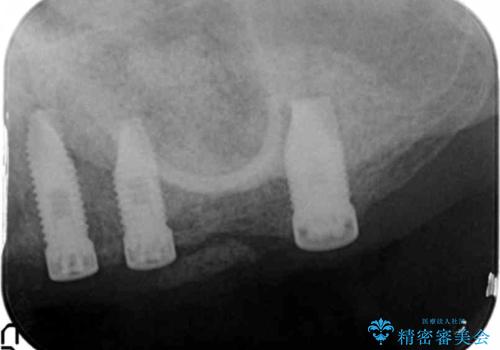

禁煙指導と歯周病治療後、左上臼歯部のソケットリフト(上顎洞底挙上術)及びインプラント治療(左上457埋入)を行いました。

インプラントが長持ちするように、角化歯肉(歯ブラシが当たっても痛くない固くしっかりした歯茎)の移植(遊離歯肉移植術:FGG)も行いました。

インプラントの種類:スプラインツイスト(HAコーティング)

固定様式:スクリュー固定